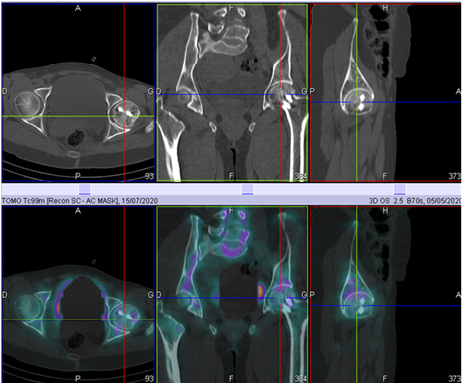

The incidences carried out during the flow phase and the blood pool phase did not demonstrate a clearly individualizable perfusion or uptake anomaly regarding the two hips (Figure 1). At the delayed phase, a unilateral hyperfixation was objectified to the left femoral head, the complement of which by SPECT - CT allowed an analysis of the sphericity of the femoral head with the possibility of staging of osteonecrosis in stage II according to the classification of Arlet and Ficat (Figure 2). The patient subsequently underwent a total left hip arthroplasty with favorable outcome.

Figure 1 The flow or angiographic phase and the blood pool phase do not objectifying a clearly individualizable perfusion or uptake anomaly regarding the two hips. The delayed phase objectifying a unilateral hyperfixation on the left femoral head.